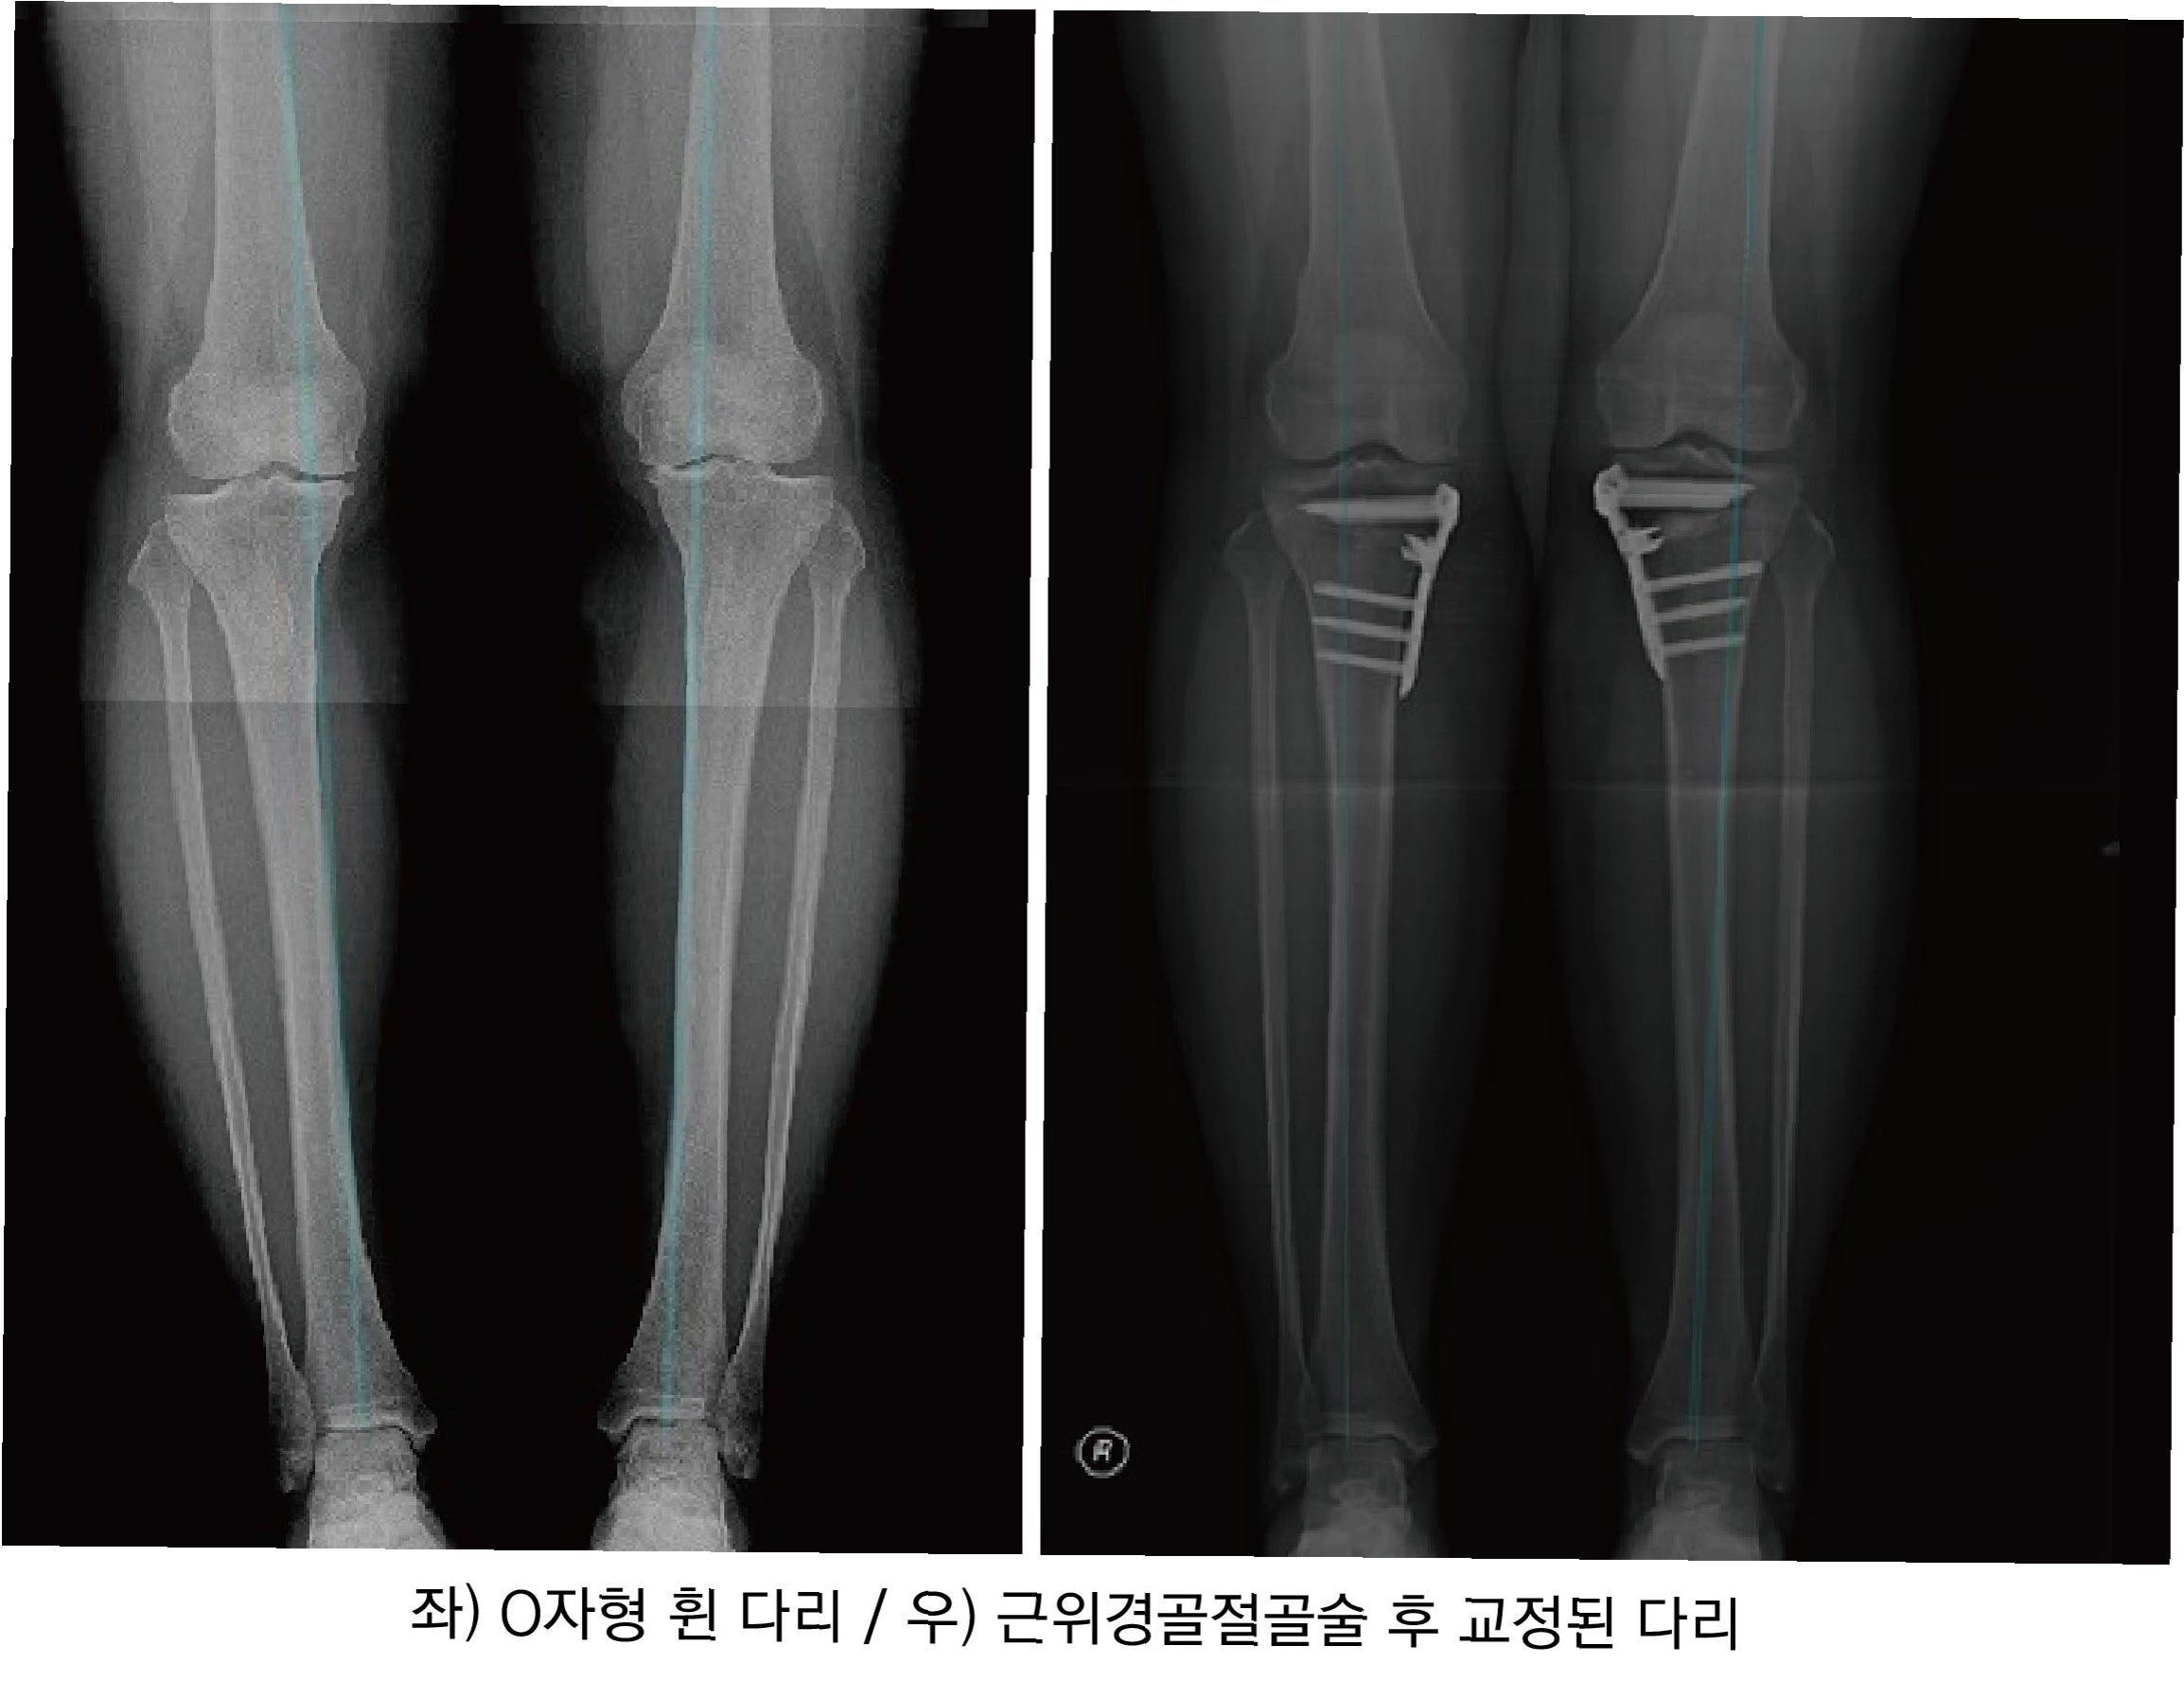

관절염은 초기, 중기, 말기로 구분됩니다. 초기에는 간헐적인 통증과 부종이 나타나며, 이때는 체중 관리, 적절한 운동, 약물치료가 권장됩니다. 중기에는 통증 빈도가 잦아지고 엑스레이 상 관절 간격 좁아짐과 골극 형성이 뚜렷해지며, 정기적인 병원 방문과 치료가 필요합니다. 말기에는 관절 간격이 거의 붙을 정도로 좁아지고 골 변형이 심해져 보존적 치료 효과가 떨어지므로 수술적 치료를 고려해야 합니다. 환자의 상태에 따라 관절내시경, 교정 절골술, 인공관절 치환술 등 다양한 수술 방법이 적용될 수 있습니다.